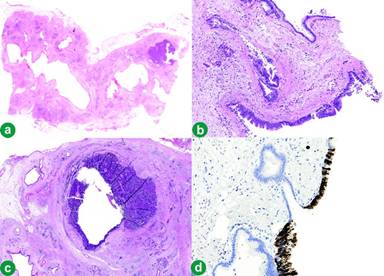

Histopathology demonstrated IPMN, positive for CDX-2 with oncocytic metaplasia, indicating mixed intestinal and oncocytic subtypes. There was invasive carcinoma arising from the IPMN with two distinct phenotypes (Figure 2). The first had atypical cells with a glandular architecture and mucin production with prominent invasive signet ring cell areas and foci of necrosis. This was positive for MUC1, CDX2 and CK20, consistent with an invasive signet ring cell and mucinous adenocarcinoma.

Figure 2. a. Part of the lining of the cyst showing neoplastic glands with oncocytic changes (haematoxylin and eosin stain x5). b. Part of the lining of the cyst showing low branching epithelium with high grade dysplasia (haematoxylin and eosin stain x10). c. Solid component of invasive carcinoma showing typical invasive ductal carcinoma (top right and carcinoma with neuroendocrine differentiation left) (haematoxylin and eosin stain x5). d. Solid cystic component of invasive carcinoma and IPMN showing focal positivity with chromogranin A in nests of neuroendocrine carcinoma (immunohistochemistry: chromogranin A stain x5). |

The second component had cells arranged in a trabecular architecture with eosinophilic cytoplasm and nuclei demonstrating prominent moulding with speckled chromatin. There was positive staining for synaptophysin and focal staining for chromagranin A (Table 1), diagnostic of a neuroendocrine carcinoma. The neuroendocrine carcinoma appeared to be arising from the IPMN. The background pancreatic parenchyma was highly atrophic and fibrotic with cystically dilated ducts. Molecular testing for K-ras showed that both tumours were wild type for K-ras.